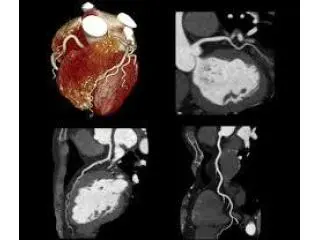

Cardiac CT scan Bradford Melbourne

Northside Imaging provides specialised cardiac imaging to aid in the accurate assessment of health of the heart and early detection of conditions that can cause heart disease. Cardiac CT Scan Bradford utilises the latest technology for computed tomography to create precise images of the coronary arteries and the heart to help detect structural and blockage.